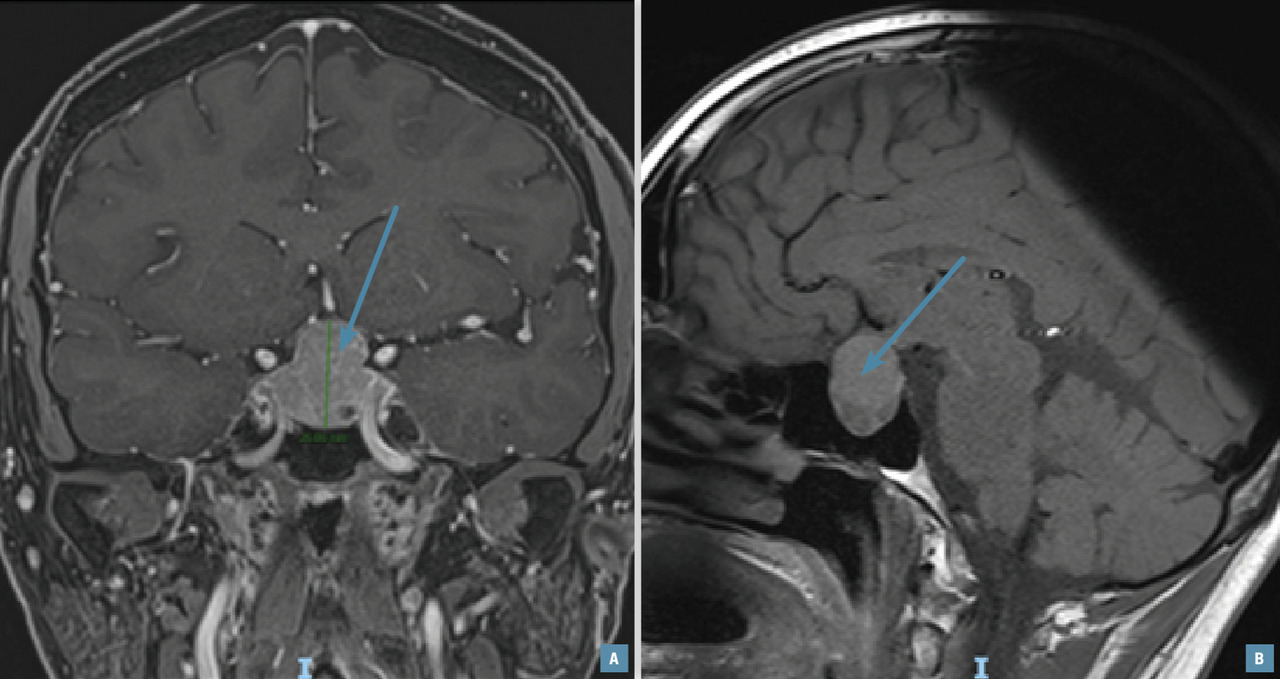

Lors de l’exploration d’une aménorrhée secondaire, une IRM hypophysaire (fig. 1) doit être réalisée en cas d’hypogonadisme hypogonadotrope, avec ou sans hyperprolactinémie.

Cet examen peut mettre en évidence des tumeurs de la région hypothalamo-hypophysaire, en particulier un adénome à prolactine, un méningiome ou un craniopharyngiome. En cas d’aménorrhée dite fonctionnelle ou nutritionnelle, l’IRM est normale ; ce diagnostic est retenu après avoir éliminé les causes organiques.

Risque tumoral

Il est important d’éliminer une tumeur de la région hypothalamo-hypophysaire avant la mise en place d’un THS devant un hypogonadisme hypogonadotrope. En effet, l’enquête étiologique permet d’éviter des complications secondaires à l’évolution tumorale, en particulier une atteinte visuelle par compression du chiasma optique.